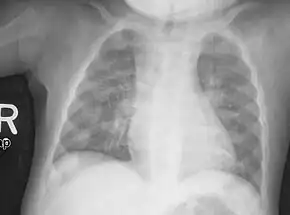

Wrist X-ray showing changes in rickets. Mainly cupping is seen here.

Chest X-ray showing changes consistent with rickets. These changes are usually referred to as "rosary beads" of rickets.

• Radiography typically show widening of the zones of provisional calcification of the metaphyses secondary to unmineralized osteoid. Cupping, fraying, and splaying of metaphyses typically appears with growth and continued weight bearing.[41] These changes are seen predominantly at sites of rapid growth, including the proximal humerus, distal radius, distal femur and both the proximal and the distal tibia. Therefore, a skeletal survey for rickets can be accomplished with anteroposterior radiographs of the knees, wrists, and ankles.[41]